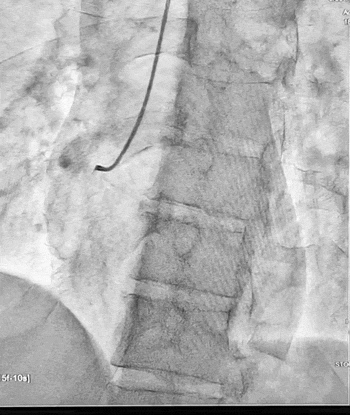

Ургентна коронароангіографія - LCA- помірно виражена, без явищ стенозування на всьому протязі. Відмічаються поодинокі колатеральні гілки в дистальний сегмент RCA. RCA- помірно виражена. Відмічається дисекція інтими в ділянці гирла. В проксимальному сегменті - гілок не виявлено. В середньому сегменті - оклюзована за рахунок великої кількості тромботичних мас.

Стентування визнано недоцільним, обрану консервативну тактику ведення пацієнта. Враховуючи стабільну гемодинаміку тимчасову ЕКС не проводили, але тримали стимулятор напоготові.

Яка причина ІМ у даного хворого? Цей випадок схожий на ось цей, коли у молодого пацієнта без кардіологічного анамнезу оклюзія коронарної артерії виникла на фоні екстремальних навантажень (змагання з пауерліфтингу). Ми не знаємо стан артерії нашого сьогоднішнього пацієнта до події: можливо, в проксимальному відділі ПКА вже була присутня гемодинамічно незначуща атеросклеротична бляшка, яка і виявилась “слабким місцем”, що при підвищенні тиску в момент наванатаження розірвалась і призвела до відшарування інтими [1,2,3].

Яка подальша тактика ведення такого пацієнта? Зазвичай у випадку дисекції коронарної артерії обирається косервативна тактика [1], і подальше лікування включатиме тривалий прийом подвійної антиагрегантної терапії, статинів, антагоністів альдостерону, іНЗКТГ-2. Доцільно провести контроль ЕхоКС через 1 та 3 місяці, при наявності симптомів ІХС - контрольну ангіографію коронарних артерій через 1-3 місяці.